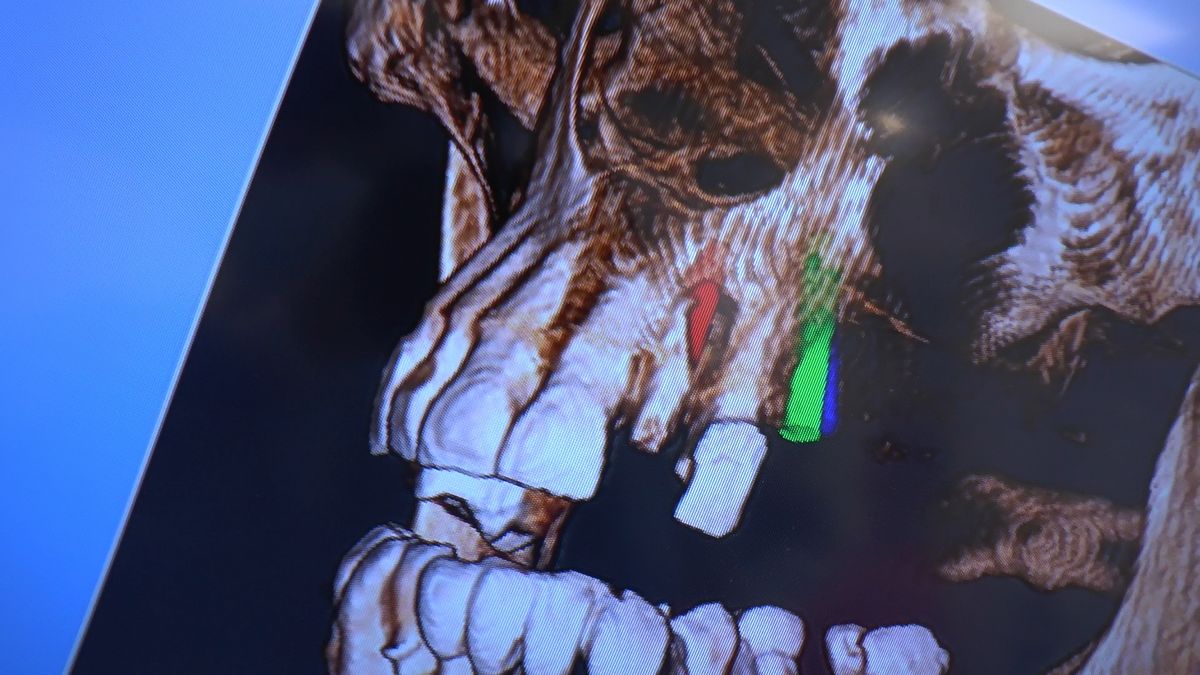

W ostatni weekend czerwca 2018 roku kursanci II Sezonu Preludium Implantologii odbyli piątą, finałową sesję, która w całości podporządkowana była praktyce. W ciągu dwóch dni zabiegowych Lekarze uczestniczący w szkoleniu przeprowadzili szereg zabiegów pod kierunkiem dr n.med. Violetty Szycik. Wszczepili 17 implantów oraz przeprowadzili ekstrakcje i zabiegi regeneracyjne kości. Zabiegi były wykonywane także w sedacji dożylnej z udziałem specjalisty anestezjologii i intensywnej terapii dr Jolanty Grzybowskiej. Preludium implantologii to nowy program edukacyjny dla adeptów implantologii stomatologicznej, którego celem jest wprowadzenie do implantologii poprzez pozyskanie wiedzy w szerokim zakresie i uwzględnieniem szczegółów mających decydujące znaczenie dla powodzenia leczenia implantologicznego. Ale tak jak wszystkie szkolenia w Instytucie Vivadental, w tym wiodące Practiculum Implantologii, zorientowane jest na praktyce i samodzielnym wykonywaniu zabiegów pod kierunkiem Mentora. To najlepsza edukacja w medycynie zabiegowej, a zarazem najlepszy start do implantologii.